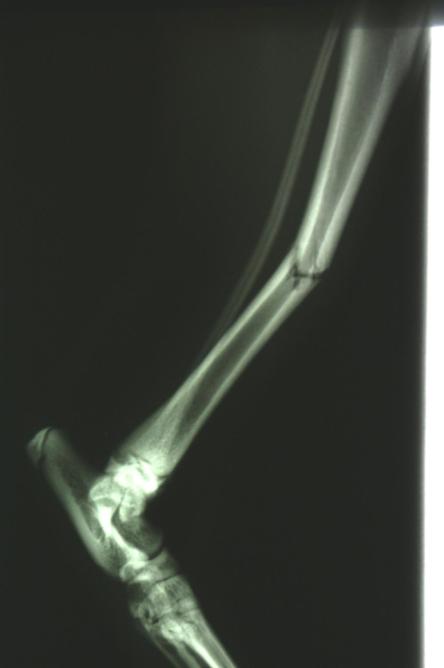

Die Fraktur ist auf Dauer konservativ nicht ausreichend stabilisierbar. Hierzu müsste das Gelenk ober- und unterhalb des Bruchs (d.h. Knie- und Sprunggelenk) immobilisiert werden, was aufgrund der Anatomie eines Katzenbeines nicht möglich ist. Zusammen mit den Besitzern wird entschieden, den Bruch mit einem sogenannten Fixateur Externe zu versorgen.

Nach vier Tagen wird nochmals ein Röntgen des Brustkorbs angefertigt, auf welchem erkennbar ist, dass sowohl Lungenblutung als auch Pneumothorax verheilt sind und eine Narkose somit möglich ist. Je zwei Stahlstifte werden ober- und unterhalb der Bruchstelle durch die Haut in den Knochen gebohrt und ausserhalb des Körpers mittels Klampen, Muttern und einem Verbindungsstift verbunden, was zusammen mit der stabilisierenden Wirkung des Wadenbeins eine ausgezeichnete Fixation ergibt. Der ausserhalb der Haut liegende Teil dieser Konstruktion wird mit einem gepolsterten „Verband“ umgeben, damit die Katze mit den Metallteilen nicht an Gegenständen hängen bleibt.